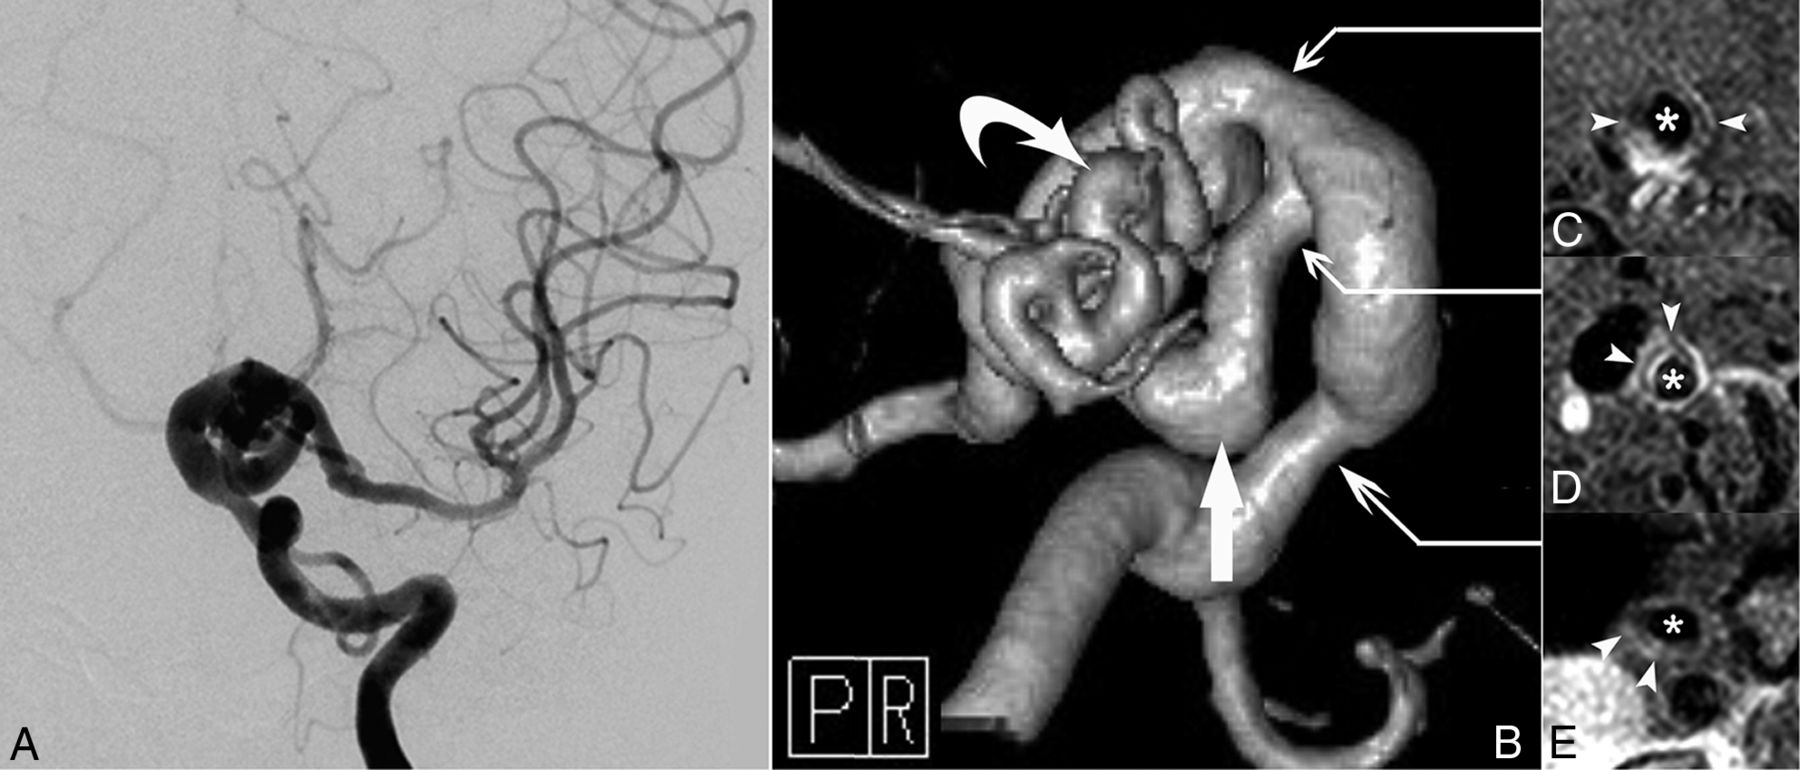

Ten patients underwent contrast-enhanced high-resolution MR imaging of the vessel wall, which detected enhancement in 6 patients with a mean age of 22.8 ± 13.2 years; the remaining 4 patients had a mean age of 57.0 ± 9.2 years (P < .001). One patient (patient 1, Fig 3) exhibited vessel wall enhancement at both 8 and 12 years of age, with no major change in the enhancement pattern. Vessel wall imaging revealed that the stenotic segment exhibited either an eccentric or concentric wall thickening (Fig 4) as well as a potential enhancement of the parent artery and aneurysm neck (Fig 5).

Evolution of vessel wall enhancement with aging in a patient with PHACE syndrome (patient 1, an 8-year-old girl). A and B, Left ICA angiography (anteroposterior and oblique views) reveals tortuosity in the left distal ICA with a small and long A1 segment. C and D, Noncontrast and contrast-enhanced vessel wall imaging at 8 years of age demonstrates vessel wall enhancement and slight vessel wall thickening (arrow in D). E and F, Vessel wall imaging at 12 years of age shows a similar vessel wall enhancement pattern (arrow in F).